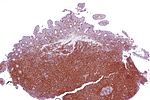

MCL is a subtype of B-cell lymphoma, due to CD5 positive antigen-naive pregerminal center B-cell within the mantle zone that surrounds normal germinal center follicles. MCL cells generally over-express cyclin D1 due to a t(11:14)[3] chromosomal translocation in the DNA. Specifically, the translocation is at t(11;14)(q13;q32).[4][5]

The immunophenotype profile consists of CD5+ (in about 80%),[10] CD10-/+, and it is usually CD5+ and CD10-.[11] CD20+, CD23-/+ (though plus in rare cases). Generally, cyclin D1 is expressed but it may not be required. Cyclin D1 negative mantle cell lymphoma can be diagnosed by detecting SOX11 marker. The workup for Mantle cell lymphoma is similar to the workup for many indolent lymphomas and certain aggressive lymphomas.